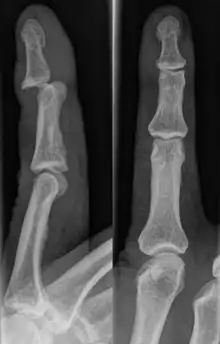

A jammed finger can generally be diagnosed via physical examination. The relative position of the bones of the finger give an indication as to potential dislocations or fractures.[3] However, it is recommended to seek medical attention regardless of whether or not a dislocation or fracture is evident.[6] This is because untreated jammed fingers can lead to future pain and stiffness, with joint surface fractures increasing the risk of arthritis.[6] The areas around the injury may be palpated in order to ascertain the areas of maximum pain.[2] If the injury is a joint injury (namely a sprain or dislocation), the point of maximum pain will be close to the joint rather than mid-phalanx (mid-bone).[2] Due to the risk of dislocations or fractures, stability testing is not recommended until after an x-ray has been conducted and the presence of a dislocation or fracture has been confirmed or rejected.[2] In extremely painful cases, a digital nerve block, where anaesthetic is injected in the web to either side of the affected finger, may be employed to enable assessment of the injury.[2] X-rays may be employed to achieve a more accurate diagnosis of a jammed finger, enabling the identification of varying types of dislocation or fractures. In order to account for all possibilities, it is recommended that a variety of views (lateral, oblique, and anteroposterior) are observed.[2]

Dislocations can be categorised based on location and type. The finger can be split into three bones and two joints in an alternating order. From the fingertip to the knuckle, these are as follows; distal phalanx, distal inter-phalangeal (DIP) joint, middle phalanx, proximal inter-phalangeal (PIP) joint, and proximal phalanx. DIP dislocations are much less common than PIP dislocations,[2] due to the “stability provided by strong collateral ligaments, palmar plates, and tendinous insertions, as well as the short lever arm of the distal phalanx”.[7] Dislocations can be categorised based on the direction that the fingertip moves in relation to the knuckle, be it in the direction of the palm (volar dislocation), or the direction of the back of the hand (dorsal dislocation). Of the two, dorsal dislocations are more common.[3] If reduction has been attempted, an x-ray of the dislocation should appear concentric if successful.[2] However, if there is a fracture present, there will be a misalignment of the joint, which will be evident from the radiograph.[2] Bach suggests a referral to a hand surgeon if a misalignment is present.[2]

Fractures are instances where the bone's structural integrity has been compromised. This is indicated by midshaft pain, as well as visual midshaft angulation or rotation.[3] As with any skeletal injury, an x-ray can be conducted to verify the presence of a fracture.[1] The distal phalanx is especially vulnerable to avulsion fractures, where a fragment of bone is ripped off when the tendon separates from the phalanx.[1] Avulsion fractures are especially common following a first time dislocation.[1] These are especially concerning, as it may indicate a complete tear of the extensor digitorum tendon. If left untreated, this may lead to permanent DIP extensor lag (inability to fully straighten the finger).[8]